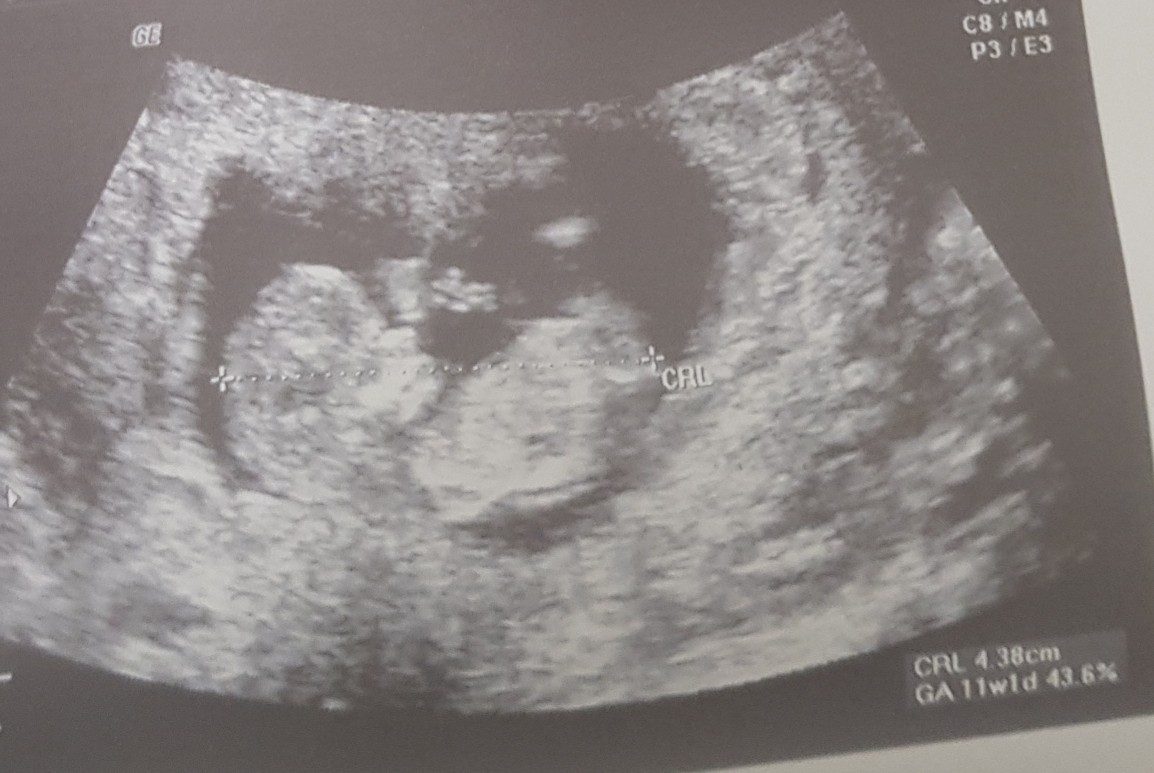

Dziewczyny ja już po! Jestem cała w emocjach! Wszystko w porzadku! Dzidziuś piękny i zdrowy, wszystko na miejscu🥰 jestem przeszczęśliwa😄 ma 5 cm i termin porodu mam na 10 listopada.

@Aleksandrettasuper wieści. Jak ja Cię rozumiem z tą lekkością 🥰. Ja też od mojego wyszłam kg kilo lżejsza i szczęśliwa. Dzidziol ma 4.3 cm, kość nosowa pięlnie widać, przezierność karkową również, raczki nóżki też. Kazał mi być spokojną i wiecej powiedzą na prenatalnych. Aaaa i prawdopodobnie siusiak ;).